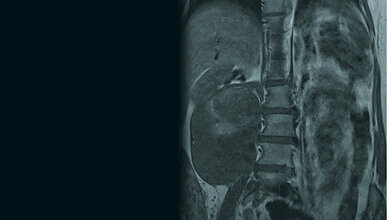

MRT und Tiefenhyperthermie-System

Das weltweit erste voll digitale Magnetresonanztomographiegerät (MRT) in Kombination mit einem neu entwickelten Tiefenhyperthermie-System. Prof. Dr. Lars Lindner (re.), Dr. Bassim Aklan LMU-Klinikum München/D. Lauffer

Kombination MRT und Tiefenhyperthermie-System

Nach erfolgreicher Antragsstellung bei der Deutschen Forschungsgemeinschaft und nach über zweijähriger Entwicklungs- und Bauphase geht in diesem Frühjahr das weltweit erste voll digitale Magnetresonanztomographiegerät (MRT) in Kombination mit einem neu entwickelten Tiefenhyperthermie-System am Klinikum der Universität München in Betrieb. Bisher erfolgt die Temperaturmessung während der Behandlung über Temperatursensoren, die entweder in den Tumor oder in natürliche Körperhöhlen in der Nähe des Tumors eingeführt werden. „Über die simultane Messung von temperaturempfindlichen MRT-Signalen erhoffen wir uns zukünftig eine möglichst genaue und nicht-invasive Erfassung der Temperatur im gesamten Tumorvolumen während der Behandlung“, erklärt Dr. Bassim Aklan, der als Medizinphysiker das Gerät betreuen wird. Da gezeigt wurde, dass die Behandlungsergebnisse mit der im Tumor erzielten Temperatur korrelieren, wäre durch das neuartige Hybridsystem mit exakter Temperaturkontrolle eine weitere Verbesserung der Behandlungsergebnisse möglich. Durch eine möglichst große Öffnung des MRT-Tunnels, einen aufklappbaren Hyperthermieapplikator sowie eine Videopräsentation am Kopfende des Patienten erhoffen sich die Kliniker zudem einen verbesserten Patientenkomfort.